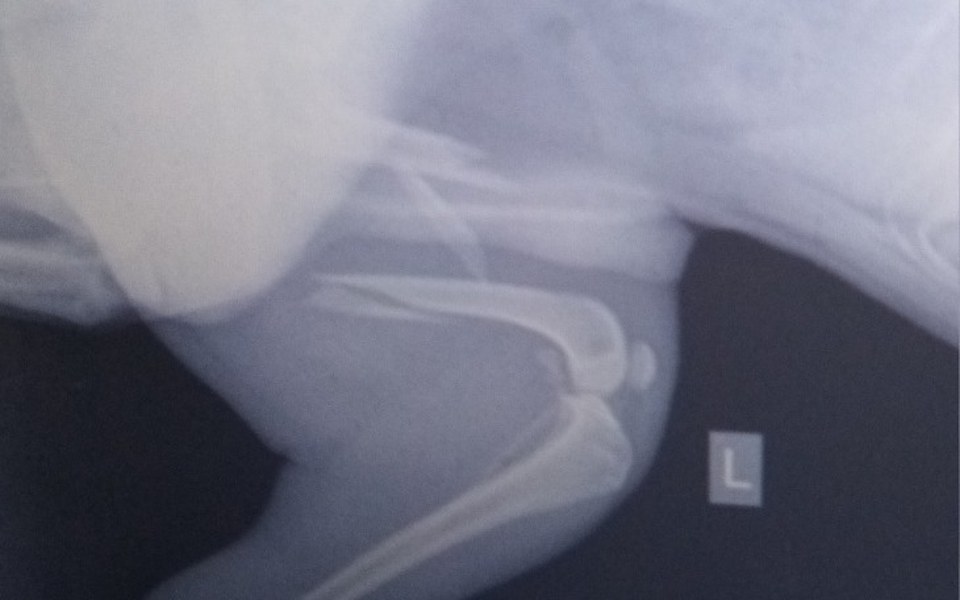

Spike został potrącony przez samochód i, ma złamaną kość z przemieszczeniem łapy tylnej na przejściu dla pieszych. Kierowca bez zastanowienia odjechał i nawet nie podszedł zobaczyć szy pies żyje.